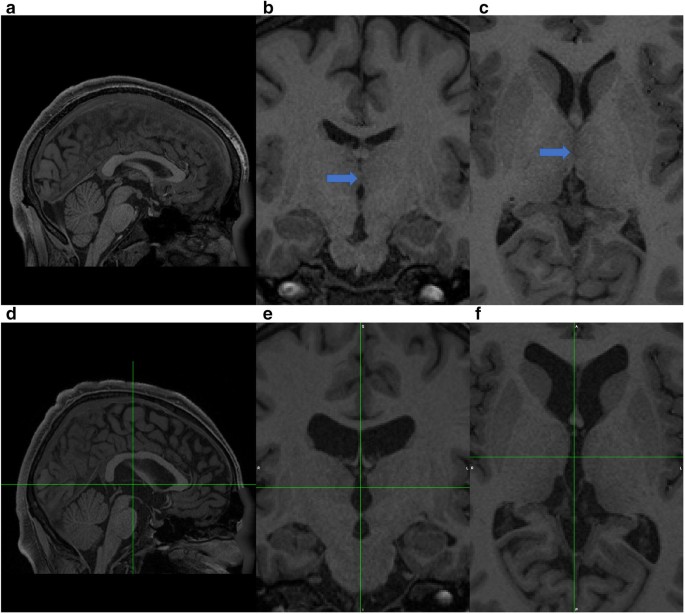

thalamic massa intermedia duplication

ruptured massa intermedia secondary to

the double massa intermedia abstract

american journal of neuroradiology